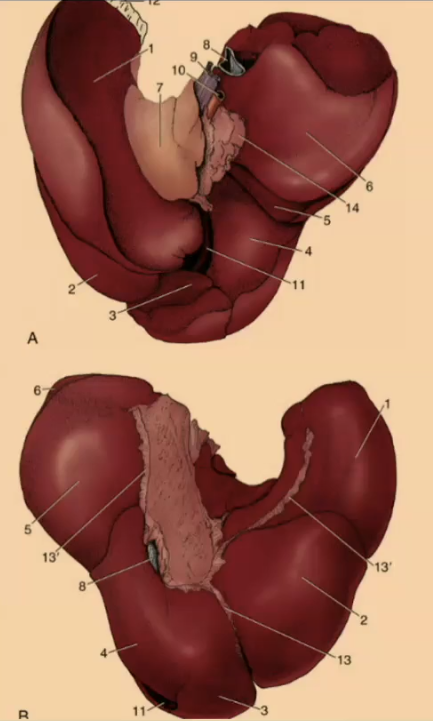

How many lobes are there to the liver?

4

What are the 4 lobes of the liver?

Left, Quadrate, Right, Caudate

#2?

Medial

#1?

Lateral

#3?

Quadrate

#4?

Medial

#5

Lateral

#6 & #7

Caudate

What produces bile?

Liver

#2

Bile duct

#1

Gallbladder

What animal is there no gallbladder?

Horse

Where is the bile stored?

Gallbladder